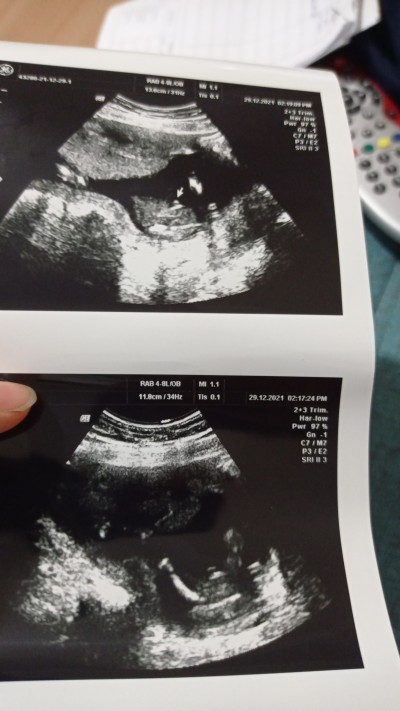

Erkek dediler ama yanılma payı olabilir mi yaa

Gebelik haftası 16

Erkek gibi duruyo cnm alttaki foto bacak arası ise net gorunuyo haftanda iyi bence net erkek

Erkek dediyse erkektir canım haftan normal neden yanılma olduğunu düşündün

Cunku pipisi küçücük ya ne biliyim

Erkek çok net zaten. Ben oğlumu öğrendiğimde değişmez mi demiştim doktora o da pipi burda nasıl değişecek diye gülmüştü o geldi aklıma :)